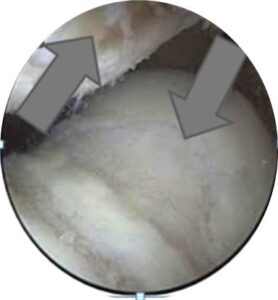

Επεμβάσεις από την άλλη μεριά «καθαρισμού» της αρθρίτιδας της επιγονατιδομηριαίας άρθρωσης, με αρθροσκόπηση έχουν πτωχά μακροχρόνια αποτελέσματα. Μπορεί και πάλι να προσφερθεί μια παροδική ανακούφιση κυρίως από την παροδική σταθεροποίηση του χόνδρου και την απομάκρυνση μικροστοιχείων φθοράς που ερεθίζουν την άρθρωση. Φαίνεται ωστόσο, στατιστικά, ότι μετά από ένα χρόνο από την επέμβαση, τα αποτελέσματα είναι απογοητευτικά. Στην κλινική μας χρησιμοποιούμε την αρθροσκόπηση κάποιες φορές, κατά την έναρξη της επέμβασης, για επιβεβαίωση των ευρημάτων μας και του θεραπευτικού πλάνου